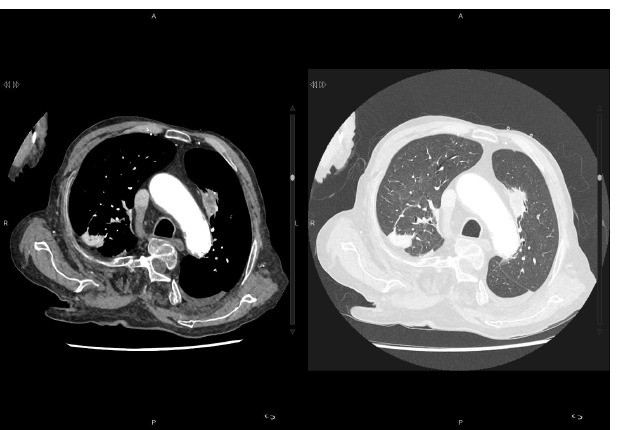

[A simple cellulitis after pruning the garden? A case report].

[修剪花园后的单纯蜂窝织炎? 一份病例报告]。